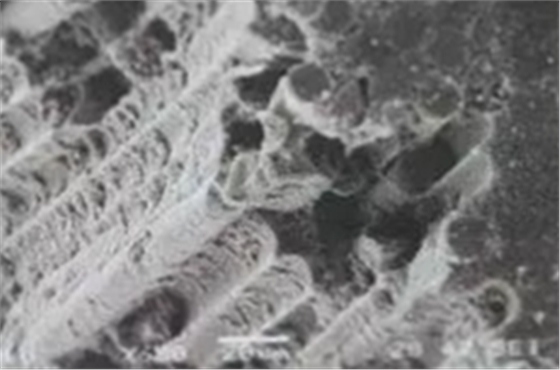

(表面微觀結(jié)構(gòu)(SEM))

為了提高固位力,纖維樁選擇考慮到三個(gè)因素:一是透明度,二是表面處理(粗化和硅烷預(yù)處理),三是固位形態(tài)的設(shè)計(jì)。特別是纖維樁根端部分的螺紋型結(jié)構(gòu)可顯著提高樁在根管內(nèi)的機(jī)械固位,防止纖維樁脫落。